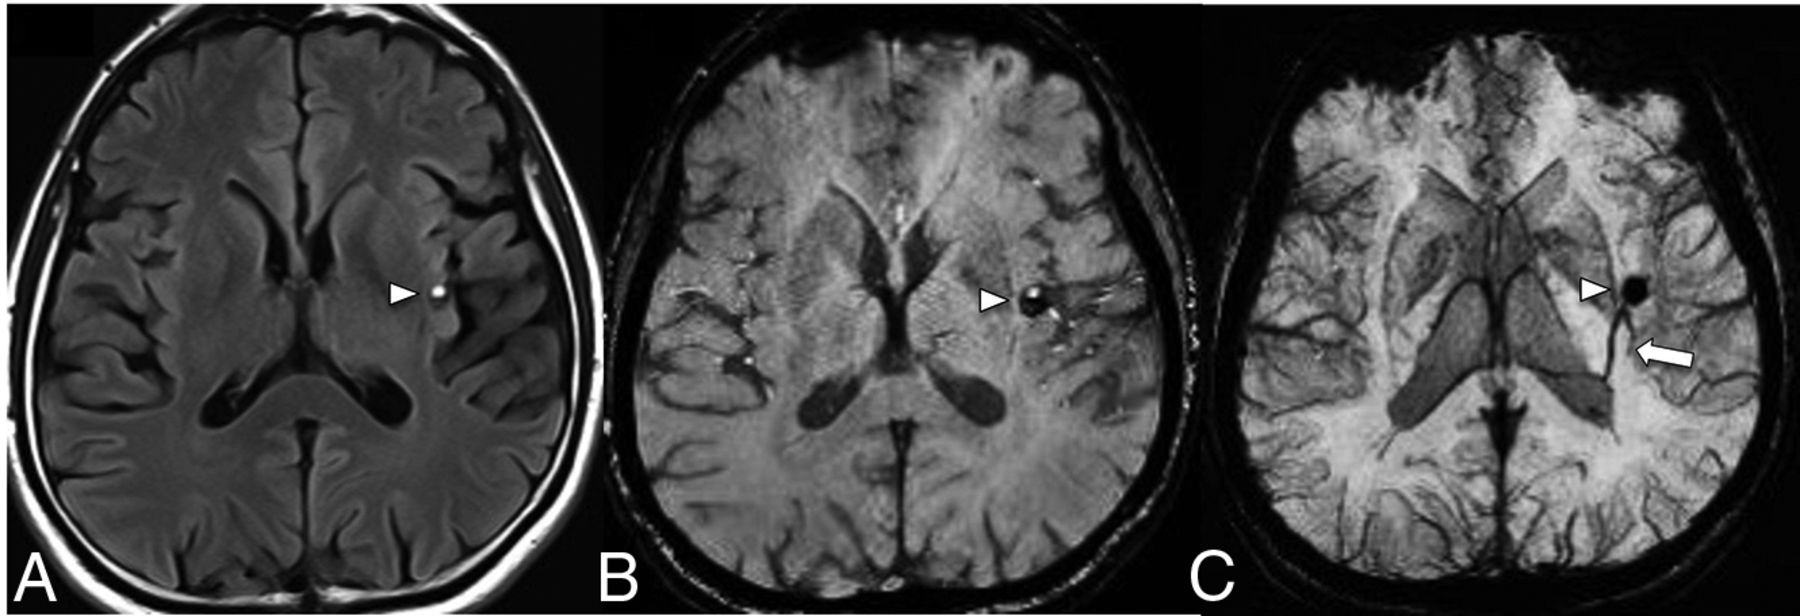

The triggered angiogenesis, which forms fragile vessels prone to hemorrhage as well as recurrent cycles of angiogenesis and microbleeds ultimately lead to the formation of CCMs.10 The following anatomic factors predispose to the development of CCMs within the drainage territory of a DVA: infratentorial DVA location, drainage of the collector into a deep vein, torsion of the draining vein, ≥5 medullary veins draining into a collector, stenosis of >55% of the medullary veins, and an acute angle between the medullary and the collector vein of ≤106.5°.8,11⇓-13 Note that most of the above-mentioned anatomic factors contribute to a decreased outflow of the DVA, thus supporting a venous congestion model of the formation of CCMs in the vicinity of a DVA. Systematic factors such as major infectious illness, chronic inflammatory disorders, and radiation exposure/treatment are also implicated in the formation of CCMs.12 The proinflammatory state is believed to promote thrombosis within the DVA, raising the venous pressure to promote an environment for CCM formation.12 Topographical location of CCMs are important as cortical or juxtacortical location or limbic involvement are more prone to seizure.14 Brainstem CCM may cause cranial neuropathy through the involvement of the cranial nerve nuclei, intra-axial cranial nerve pathway or even direct extension into the cisternal cranial nerves (Fig 2).15 Hemorrhagic propensity of CCM hemorrhage is based on the history of prior hemorrhage and this can be quantitatively analyzed through the CCM hemosiderin burden and its evolution over time on quantitative susceptibility mapping (QSM).16,17 Higher mean susceptibility value on QSM positively correlates with patient age and prior hemorrhagic episodes, whilst patients with clinically stable CCM demonstrate lower mean susceptibility value (Fig 3).16,17

A middle-aged patient with new-onset ataxia. T1WI (A) and SWI MIP (B) show a CCM in the right superior cerebellar peduncle (arrowheads) and a large left cerebellar DVA with the collector vein (arrow) draining into the transverse sinus. Quantitative susceptibility mapping (C) analysis of the CCM shows a high mean susceptibility value of 858 parts per billion (with threshold). An ROI with a red boundary represents the exclusive object boundary, and the purple area represents thresholded pixels (150 parts per billion). SWIM (Siemens) parameters: TE = 20.00 ms; TR = 27.00 ms; flip angle = 150; resolution = 0.937 × 0.937 ×2.5 mm. Images courtesy of Dr E. Mark Haacke.